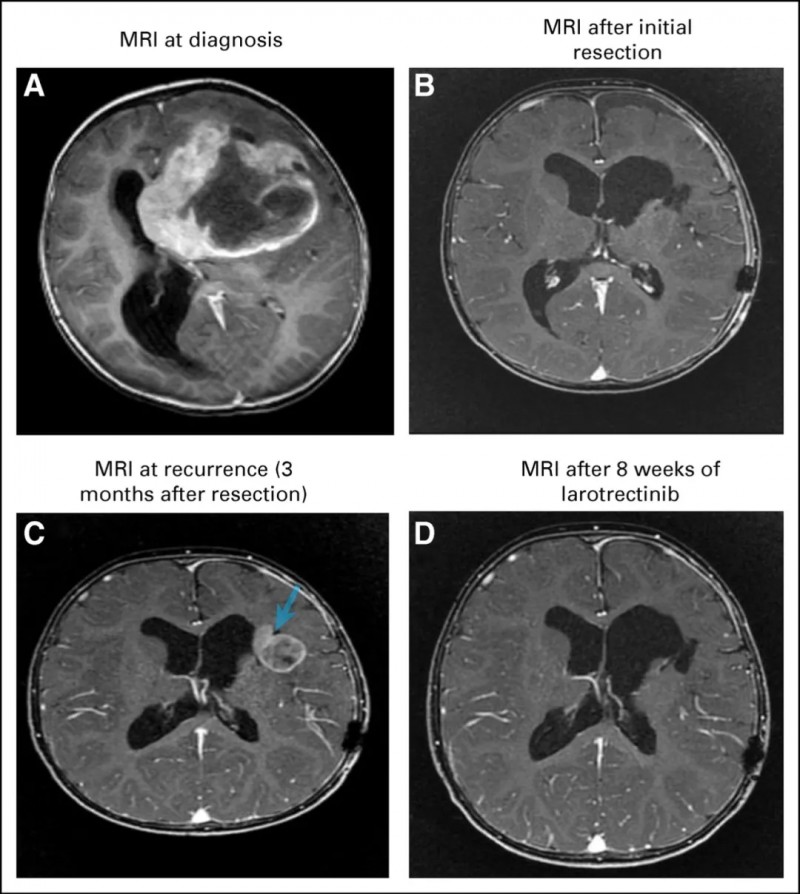

一名18个月大的沙特阿拉伯女婴确诊为胶质母细胞瘤,手术后按个月复发,因为她的父母知道生存期并不乐观,所以拒绝了副作用过大的放化疗,在基因检测后发现存在ETV6-NTRK3融合,于是决定入组拉罗替尼临床试验,一线接受拉罗替尼治疗,第8周,MRI显示肿瘤明显消退,未见不良反应。

图片来源:柳叶刀